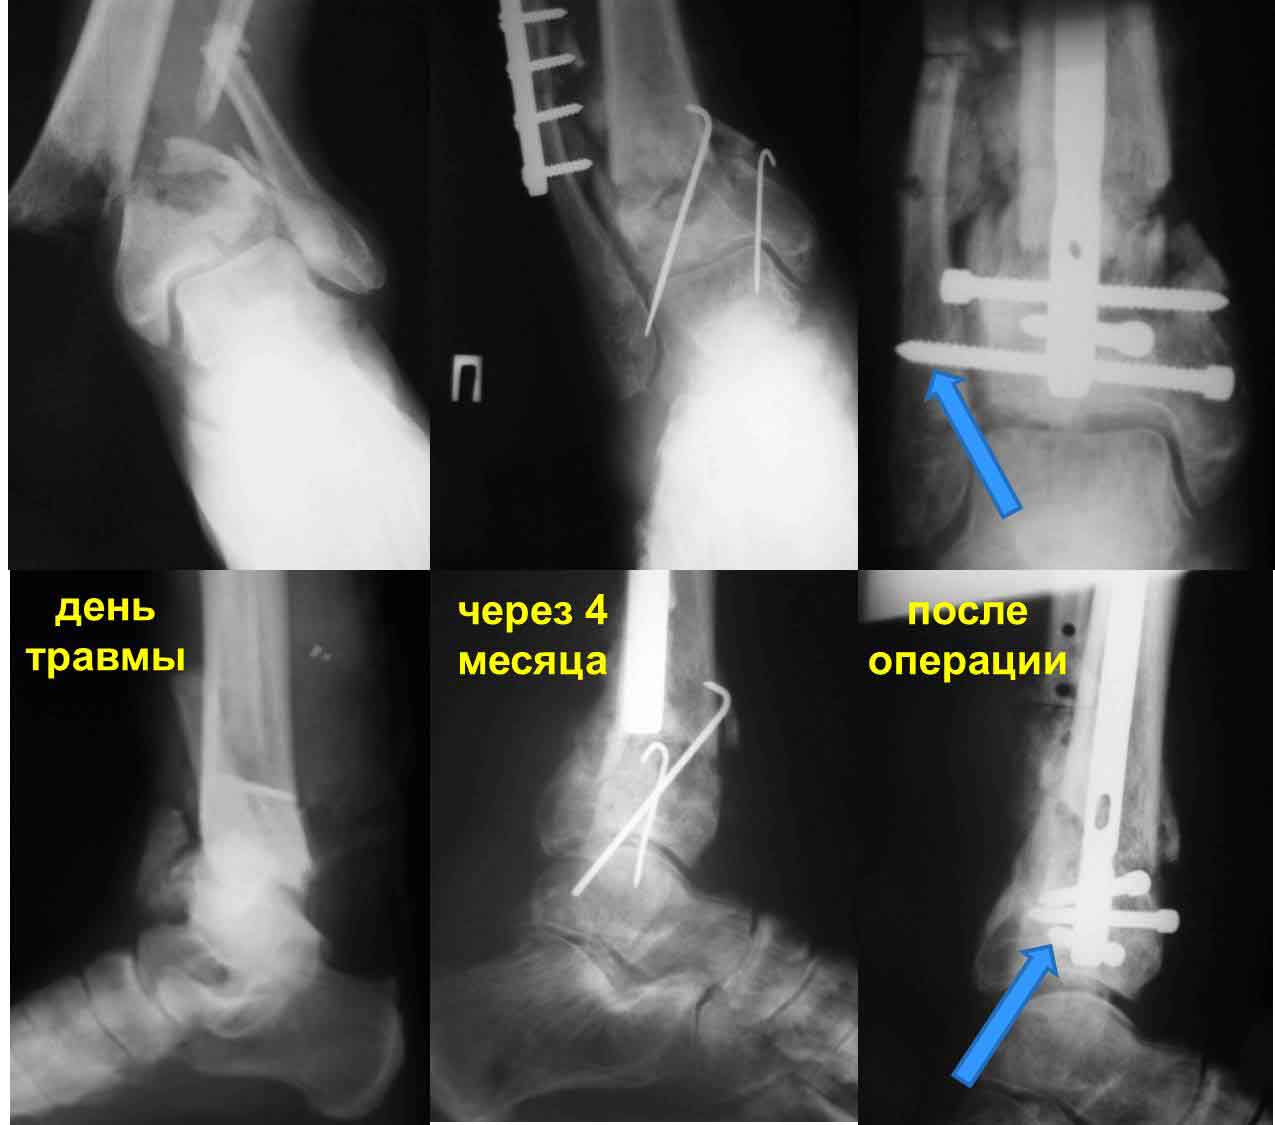

Частота ложных суставов и повторных смещений костных отломков после оперативной стабилизации переломов пилона доходит до 30%. Каждый, кто занимается лечением таких повреждений, наверняка сталкивался с такими осложнениями. Однако лечить такие осложнения в моральном, да и в оперативном плане проще, чем свежие переломы пилона (особенно Ruedi III), поскольку к этому времени становится более или менее понятной судьба голеностопного сустава. Если в достаточной мере владеете блокированным остеосинтезом, то самым оптимальным вариантом, с моей точки зрения, будет следующий. С переднемедиального и латерального доступов выполнить поперечную остеотомию большеберцовой и малоберцовой костей в плоскости параллельной плоскости голеностопного сустава на расстоянии около 3 см от самого сустава. Это минимальное расстояние, которое позволит расположить три блокирующих винта стержня. Важен выбор самого стержня. В данном случае больше всего подходит стержень ChM, имеющий на дистальном конце помимо отверстий в сагиттальной и фронтальной плоскостях и отверстия под углом в 45 градусов, причём на минимальном расстоянии друг от друга. Остетомию и последующую репозицию костных отломков мы выполняем в репозиционном спицевом аппарате. Стержень антеградный. В данном случае не вижу никаких оснований в применении ретроградного стержня, проходящего через здоровый подтаранный и через голеностопный сустав с его до конца неопределённой функцией. Образовавшийся дефект по переднемедиальной поверхности должен быть заполнен костным трансплантатом. Пример похожего случая из нашей практики - в приложенном файле.